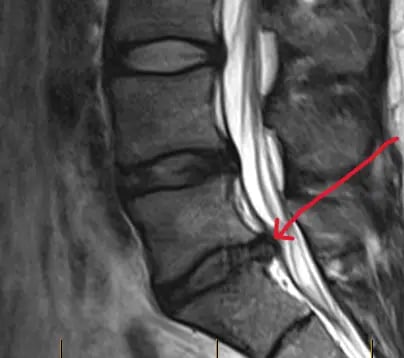

الانزلاق الغضروفي:

إعادة محاذاة الأقراص المنزاحة لتقليل الألم وتهيج الأعصاب.

يعمل علاج تخفيف ضغط الأقراص الفقرية على تطبيق شدٍّ لطيف ومُتحكَّم فيه على العمود الفقري، مما قد يساعد على تقليل الضغط داخل الأقراص الفقرية وتخفيف الضغط عن الهياكل المحيطة مثل الأعصاب والأنسجة الرخوة.